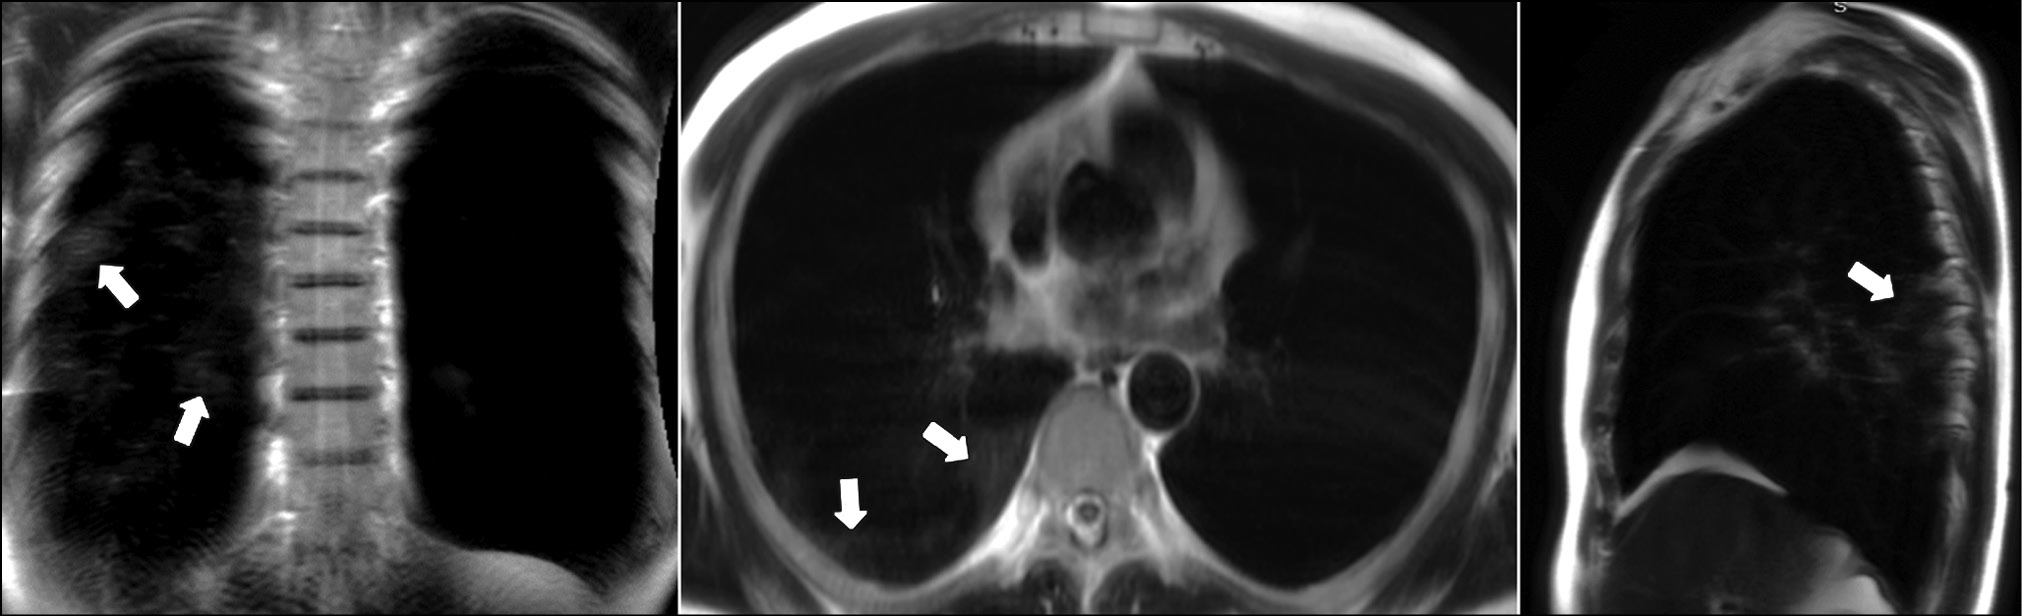

A patient (female, 45 years old) presented to the clinic on the fifth day after the onset of dry cough and mild fever up to 37.5°С. Dynamic lung MRI in the coronal plane (Fig. 1) showed an area of hyperintense signal in the lower lobe of the right lung (S9–S10), interpreted as an area of central induration (more intense signal) with a surrounding “cloudy sky” (less intense signal) during inhalation. A hyperintense signal was found in the corresponding area in the axial and sagittal planes, indicating consolidation with a “cloudy sky” along the edge of the area. At the end of exhalation, increased signal intensity was observed in the described area in the coronal plane (Fig. 2) with decreased visual size of the affected areas due to lung tissue contraction. During exhalation, no changes in signal intensity were observed in the axial and sagittal planes.

Figure 1. Dynamic magnetic resonance imaging of the lungs during inhalation in the coronal, axial, and sagittal planes. In the axial and sagittal planes, arrows point to areas of compaction. In the coronal plane, the arrow points to a “cloudy sky” (S9–S10).